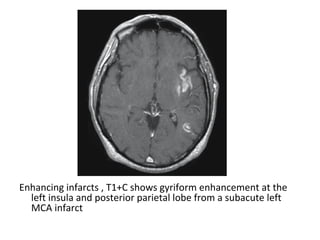

Enhancing infarcts , T1+C shows gyriform enhancement at the left insula and

posterior parietal lobe from a subacute left MCA infarct

Enhancing infarcts , T1+C shows gyriform enhancement at the

left insula and posterior parietal lobe from a subacute left

MCA infarct